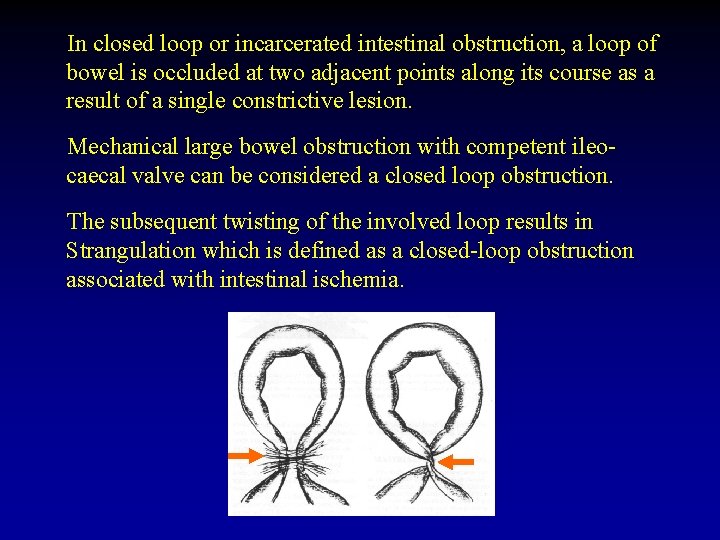

In closed loop or incarcerated intestinal obstruction, a loop of bowel is occluded at two adjacent points along its course as a result of a single constrictive lesion. Mechanical large bowel obstruction with competent ileocaecal valve can be considered a closed loop obstruction. The subsequent twisting of the involved loop results in Strangulation which is defined as a closed-loop obstruction associated with intestinal ischemia.